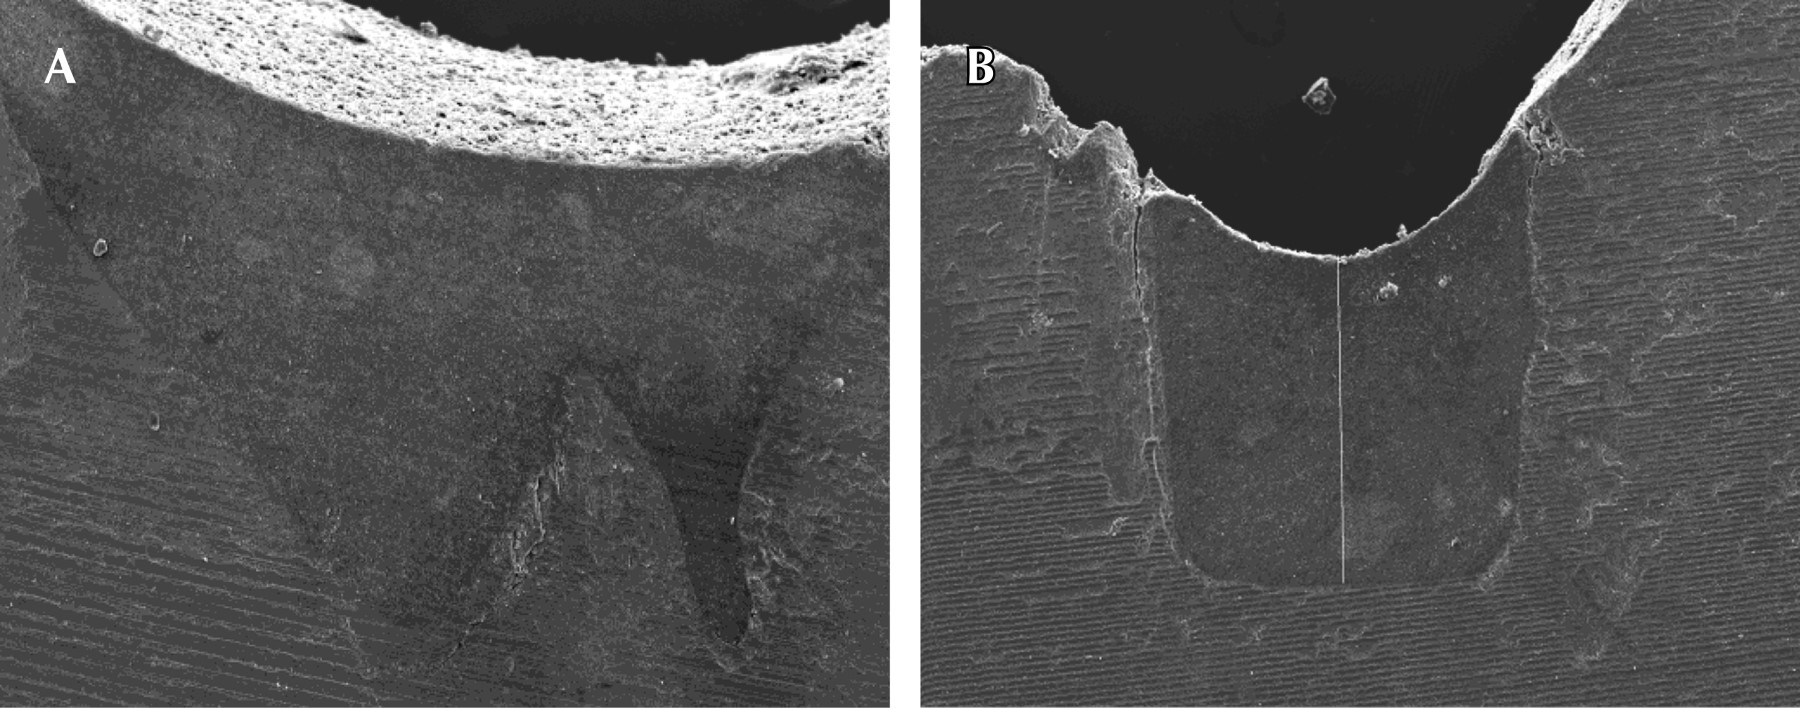

El grupo adhesivo/sellador y adhesivo/Flow, con y sin ameloplastia, alcanzó mayores valores de adaptación íntima a las paredes del surco. Las diferencias fueron significativas entre los materiales (p = 0.0009), pero no entre los tratamientos realizados a los surcos ni en el efecto de interacción (material-tratamiento al surco). El SFF fue el material que registró mayor desadaptación o zonas de desadaptación. En la Tabla 4, se observan las medias de las zonas de desadaptación del material a las paredes del surco. En la Figura 3 se observa la adaptación del adhesivo/sellador, con y sin ameloplastia, que mostraron buena adaptación con escasas zonas de desadaptación.

Sin embargo, al observar la microfotografía del sellador, con y sin ameloplastia, se evidencia buena adaptación en los dos tercios superiores del surco, no así en la zona inferior que muestra áreas de discontinuidad del material y las paredes del mismo (Figura 4).

Por otra parte, el adhesivo/sellador, sin y con ameloplastia, registró mejor adaptación del material, mientras el adhesivo/Flow con ameloplastia fue el grupo que mostró menores áreas de desadaptación.